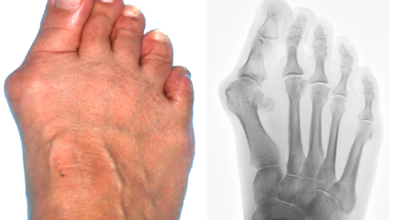

엄지발가락이 두번째 발가락 쪽으로 과도하게 휘고 엄지발가락과 관절을 이루는 중족골은 반대로 안쪽으로 치우치는 변형 되며 발가락이 발등 쪽으로 휘거나 회전(엄지발가락 축을 중점으로 내측으로 회전; 회내)하는 변형을 동반한 삼차원적인 변형을 말합니다.

육안상으로 확연하게 엄지발가락 과 같은 변형 보이며 초기에는 굳은살도 관찰되고 약간의 통증도 있습니다. 엄지발가락 돌출 부위의 통증으로 이 부위가 신발에 자극을 받아 두꺼워지고 염증이 생겨 통증이 발생합니다. 휘어지지 않은 발바닥에 굳은살로 인해 정상 보행이 어렵고 심한 경우 통증으로 인하여 신발 착용은 물론 정상 보행도 어려워집니다. 연속적으로 증상이 악화되면 엄지발가락이 겹쳐지거나 탈구 될 수도 있습니다.

엄지발가락이 옆으로 휘어 관절에 비정상적인 힘이 가해져 퇴행성 관절염이 생길 수 있죠. 그리고 엄지발가락이 지지해야 할 발바닥 압력이 2, 3번째 발가락으로 옮겨지면서 발바닥 쪽에 굳은살이 발생할 수 있고 발가락 뼈 사이의 신경이 붓고 통증이 나타나는 지간신경종이 합병될 수도 있습니다.